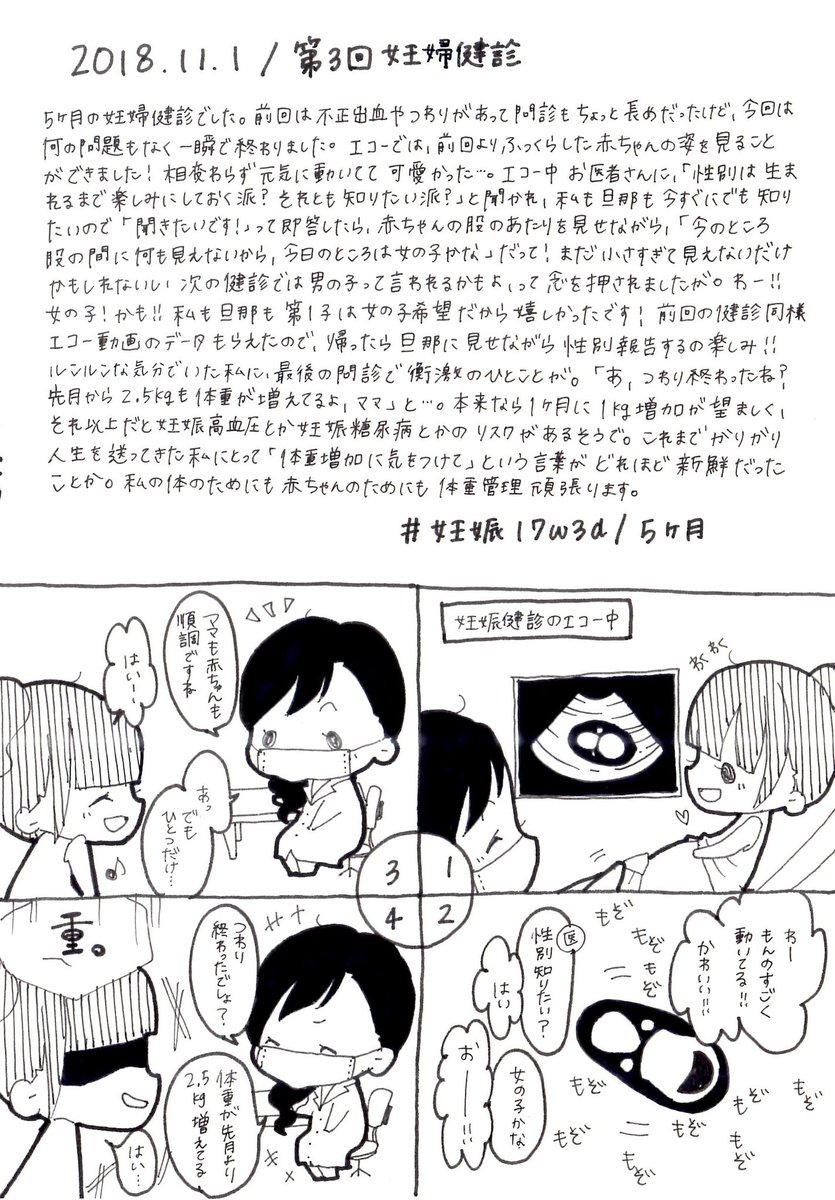

2018.11.1 だって…だってつわりが終わって、食べる喜びを思い出したんです…! お腹とエコー写真載せます、閲覧注意です! #育児漫画 #育児日記 #妊娠 #妊娠中期 #妊婦健診 #エコー #妊娠5ヶ月 #イラスト好きさんと繋がりたい #オリジナル漫画 pic.twitter.com/weFV55BdZ0

2019-08-22 14:54:55 拡大

拡大

拡大

拡大